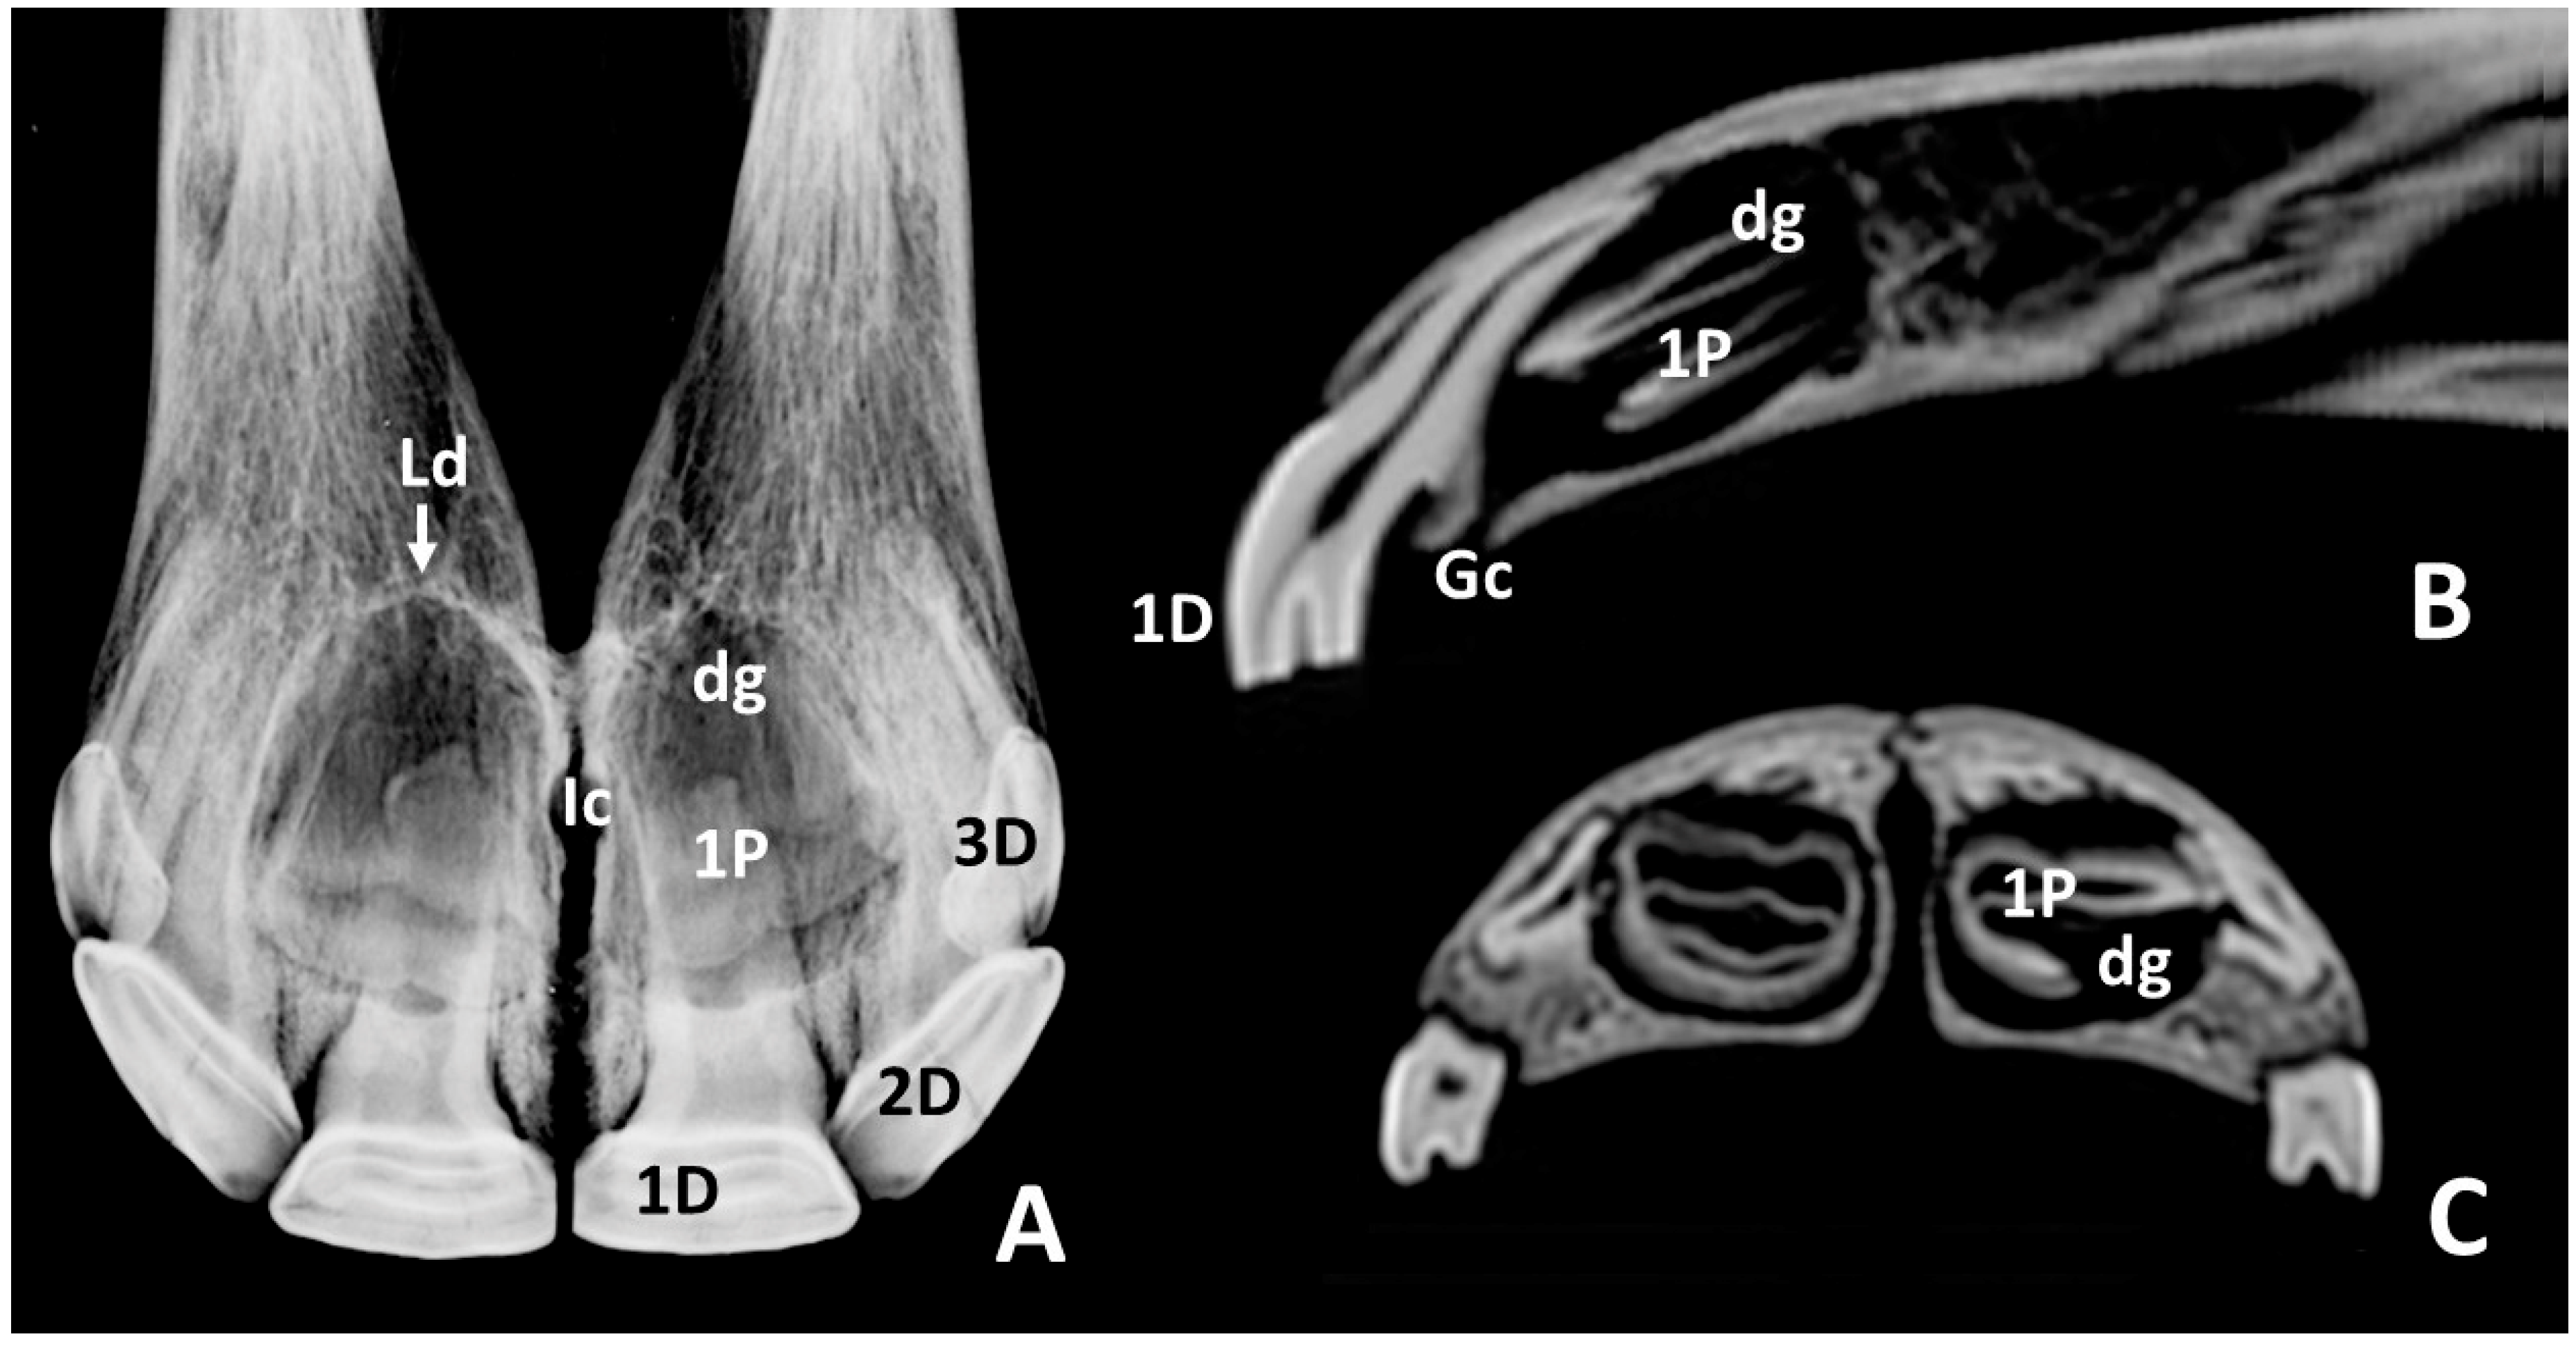

3.2. Radiographic and CT Studies

4.1. Deciduous Incisors: Radiographic and CT Studies

4.2. Permanent Incisors and Alveoli: Radiographic and CT Studies

| 1d | Dental germs, larger unerupted crowns within the incisive bone, greater radiopacity | 4 |

| 1d | 41.6 ± 1.8 | 15.1 ± 2.5 | 4.5 ± 1.4 | 35.1 ± 2.3 | 35.1 ± 2.3 | 31.2 ± 2.8 |

| 1d | 36.3 ± 6.5 | 10.9 ± 3.2 | 100.0 ± 0.0 | 88.9 ± 3.5 |